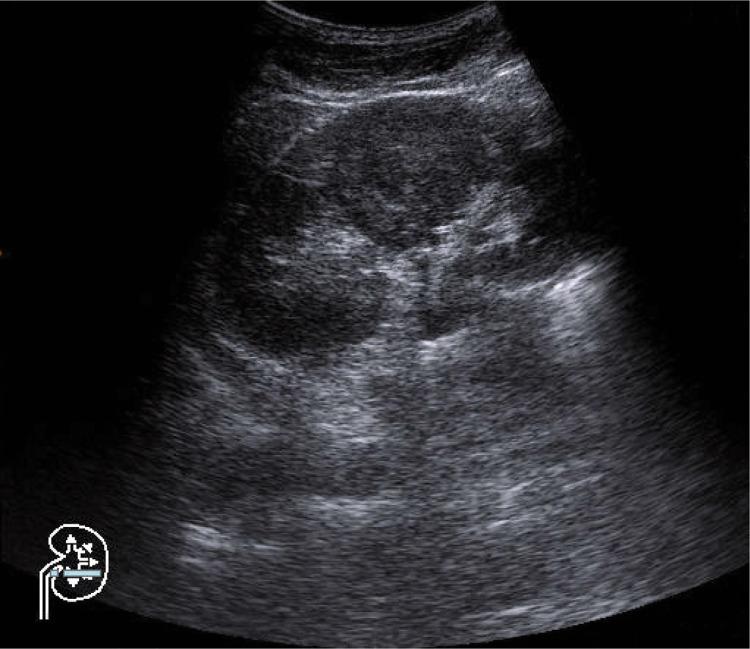

The paper presents the principles of performing proper ultrasound examinations of the urinary tract. The following are discussed: preparation of patients, type of optimal apparatus, technique of examination and conditions which its description should fulfill. Urinary track examination in adults and in children constitutes an integral part of each abdominal examination. Such examinations should be performed with fasting patients or several hours after the last meal, with filled urinary bladder.

Renal examinations are performed with the patients in the supine position. The right kidney is examined in the right hypochondriac region using the liver as the ultrasound "window." The left kidney is examined in the left hypochondriac region, preferably in the posterior axillary line. Ultrasound examinations of the upper segment of the ureters are performed after renal examination when the pelvicalyceal system is dilated. A condition necessary for a proper examination of the perivesical portion of the ureter is full urinary bladder. The scans of the urinary bladder are performed in transverse, longitudinal and oblique planes when the bladder is filled.

本文介绍了对尿路进行正确超声检查的原则。讨论了以下内容:患者准备、最佳设备类型、检查技术以及检查描述应满足的条件。成人和儿童的尿路检查是每次腹部检查的组成部分。此类检查应在患者空腹或最后一餐数小时后进行,膀胱需充盈。

肾脏检查时患者取仰卧位。右肾在右季肋区检查,以肝脏作为超声“窗口”。左肾在左季肋区检查,最好在腋后线。当肾盂肾盏系统扩张时,在肾脏检查后对输尿管上段进行超声检查。对输尿管膀胱周围部分进行正确检查的一个必要条件是膀胱充盈。膀胱扫描在膀胱充盈时在横切、纵切和斜切平面进行。